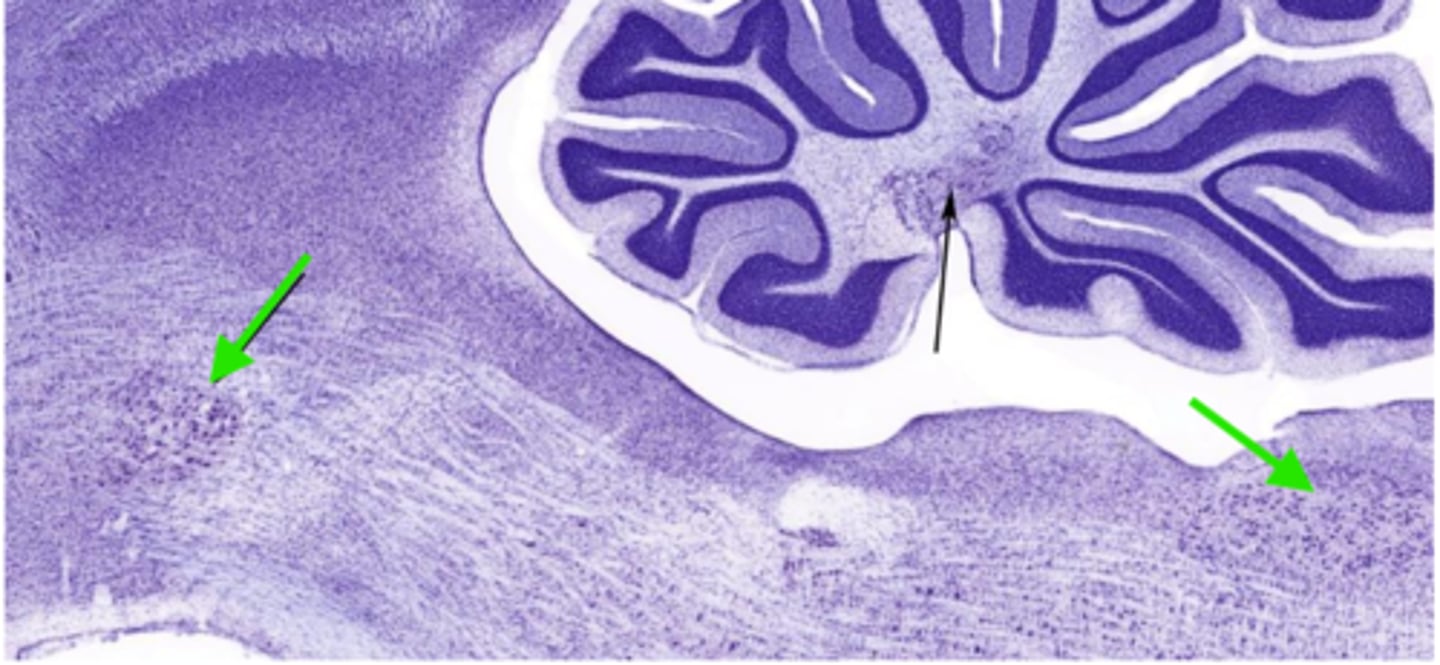

Identify the cluster of neurons at the green arrows

nucleus of the brainstem